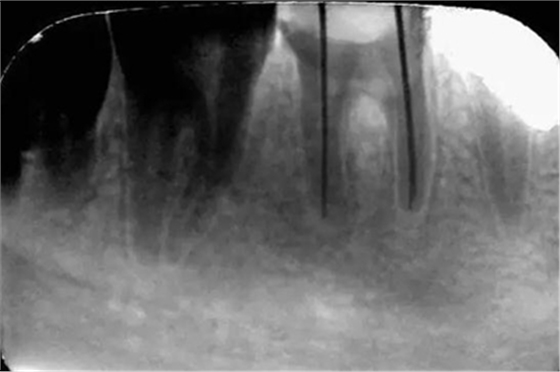

初診時X光片:根分歧炎癥懷疑有底穿,和患者交待病情和費用后開始治療。

初尖銼X光片:現(xiàn)在根測儀的準確性的卻非常之高。